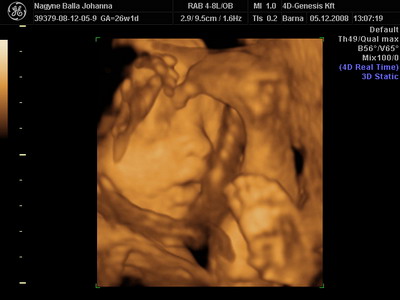

Csilla, az uh-s hölgy volt nagyon jó fej. Kérdezte, tudjuk-e ki lakik a pociban, mondtuk, kisfiú. Erre azt mondta, nézzünk rá. Kereste, Lukács mutatta, kis fütyi így, kis fütyi úgy, aztán fordult a kép, és Csilla nagy nevetve, nem is kicsi annyira ez a kis fütyi!

Akkor mérte le!